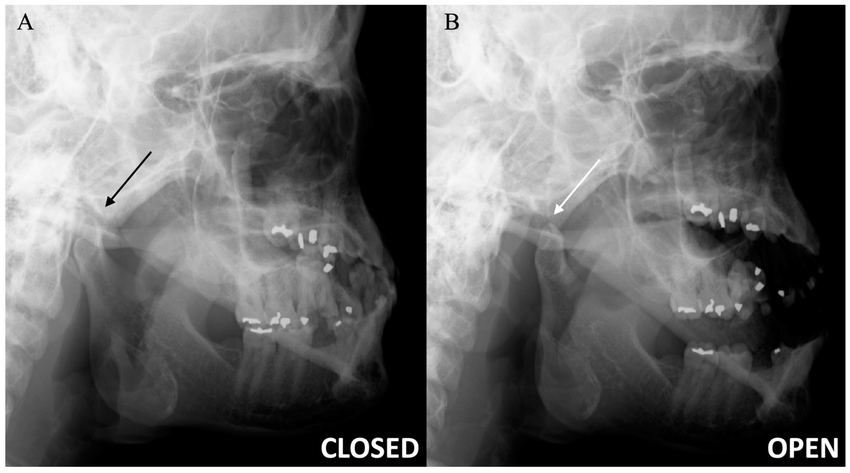

TMJ View

TMJ View (Open / Close)

The temporomandibular view allows for visualization of the articular tubercle, mandibular condyle and fossa and is thus useful to identify structural changes

TMJ Scan

investigations are of paramount importance in the diagnostic assessment of a patient with TMD. Bony changes in the TMJ like flattening, sclerosis, formation of osteophytes,